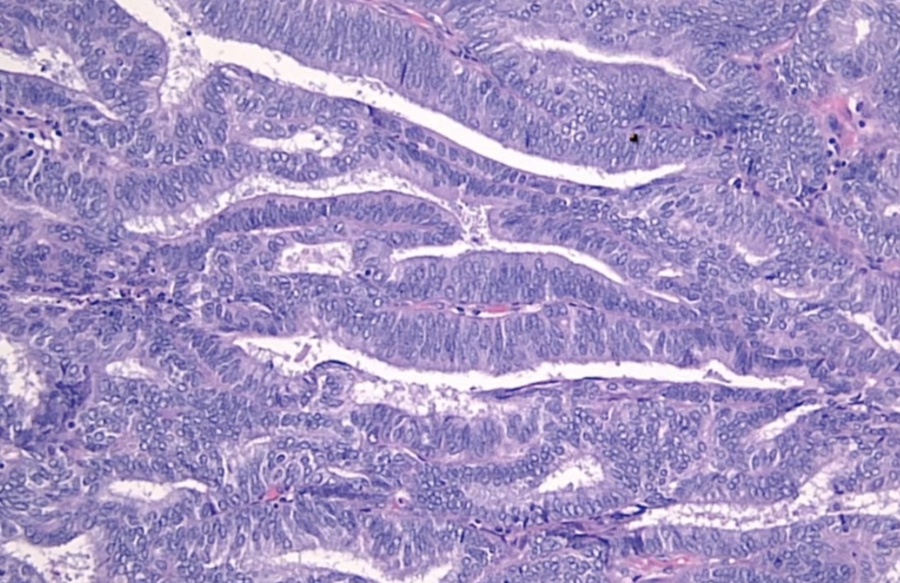

High grade dysplasia (carcinoma in situ) in the uterine cervix. The abnormal epithelium is extending into a mucus gland to the left of centre. This disease can progress to invasive cancer (squamous cell carcinoma) of the cervix:

CIN III

_CIN I to III can regress. CIS cannot regress and will proceed to invasive squamous cell carcinoma once it breaks through basement membrane.

_Carcinoma in situ is characterized by atypical changes extending through the entire thickness of the epithelium.

As it has not yet invaded the basement membrane, it is considered a precancerous lesion.